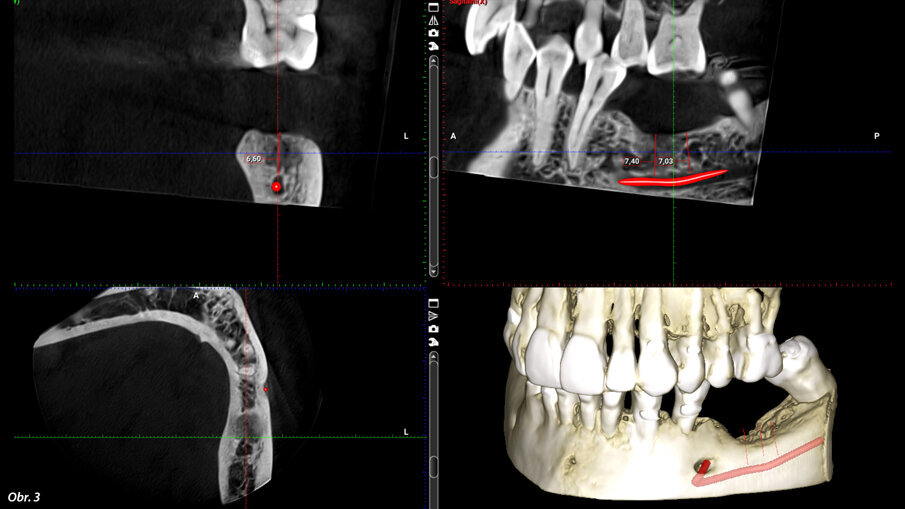

Na naše oddělení se dostavila pacientka, 52 let, s implantátem v místě 36, který byl zaveden na jiném pracovišti asi před 6 lety. Implantát vykazoval známky odhojení. Na OPG (ProMax, Planmeca) byl patrný velký úbytek kosti v okolí implantátu způsobený periimplantitidou (obr. 2). Proto byl implantát odstraněn, defekt byl exkochleován. Po 3 měsících bylo zhotovené CBCT (ProMax, Planmeca) pro plánování náhrady implantátu (obr. 3). Po zvážení všech možností (vertikální augmentace, short implant) jsme se rozhodli k zavedení tilted implantátu, který bude zaveden tak, aby míjel průběh mandibulárního kanálu (obr. 4). CBCT sken nám pomohl přesněji určit polohu mandibulárního kanálu. V programu jsem si následně vybral vhodný průměr i délku implantátu a určil jeho polohu tak, aby se vyhnul průběhu kanálu a zároveň respektoval aktuální nabídku kosti. Je velmi důležité podívat se na situaci z různých pohledů, abychom se ujistili, že jsme ošetření správně naplánovali.

CBCT sken po 3 měsících od odstranění implantátu.

Plánovaná pozice implantátu BioniQ v blízkosti mandibulárního kanálu.